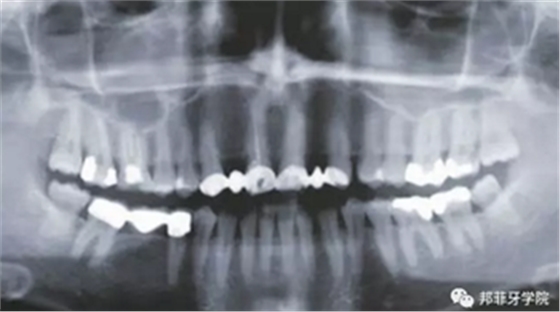

26歲女性患者,雙側(cè)上頜側(cè)切牙先天缺失,對(duì)原有修復(fù)體的“形態(tài)”、“光澤”等方面不滿意,希望重新修復(fù)(圖1&2)。12及22原為粘接橋修復(fù),11根管治療史;拆除原修復(fù)體后余鄰牙完整,未見病理性探診深度。無系統(tǒng)疾病史。患者期望值較高,告知治療流程佩戴臨時(shí)卡環(huán)義齒等(圖3)、費(fèi)用、風(fēng)險(xiǎn)后表示接受治療。

圖2:治療前全景片